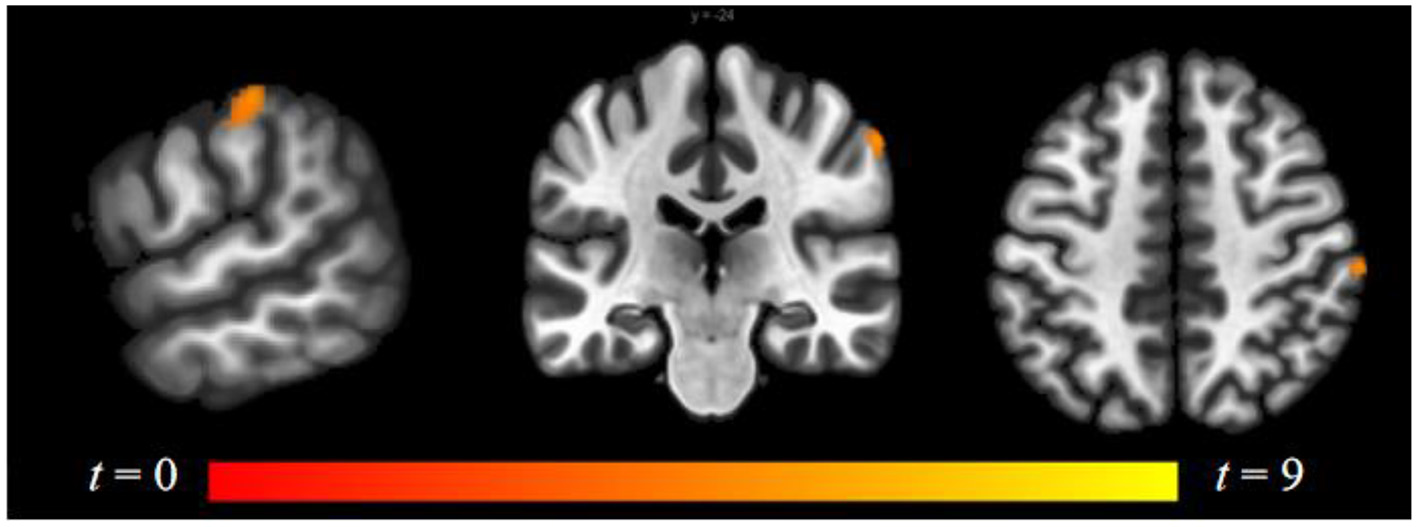

Compared to follicular women, menses women showed increased connectivity between the amygdala and supramarginal gyrus (see Figure 4 and Table 2). Follicular women did not show any regions of increased connectivity relative to menses women in the amygdala, insula, or ACG.

Figure 4

Within-group differences between menses phase and follicular phase. The hot color scale indicates higher left amygdala–right supramarginal gyrus resting-state functional connectivity (RSFC) in the menses phase than follicular phase. Coordinates are given in MNI space and statistics in t-values.

| Right supramarginal gyrus | +62 | −24 | +48 | 5.04 | 43 | |